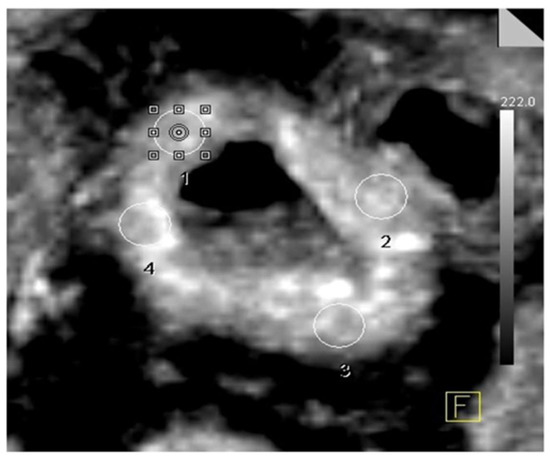

3. Results

3.2. PCT Parameters